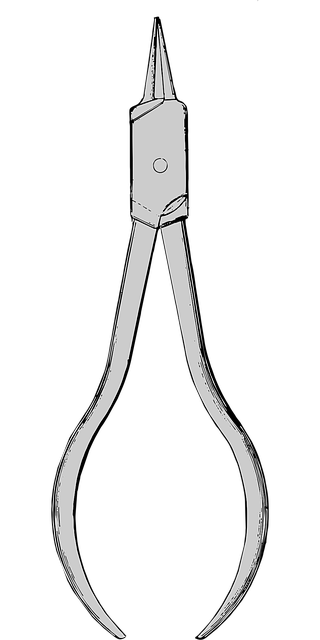

When preparing for your first orthodontic consultation with an orthodontist in McAllen, TX, it’s beneficial to take a few simple steps. Begin by gathering all your medical records and x-rays from previous dental visits. These documents will help your orthodontist understand your oral history and current state of teeth alignment. Additionally, make a list of any questions or concerns you have regarding your bite, teeth, or jaw pain. This proactive approach ensures a productive consultation where you can gain valuable insights into potential treatment options.